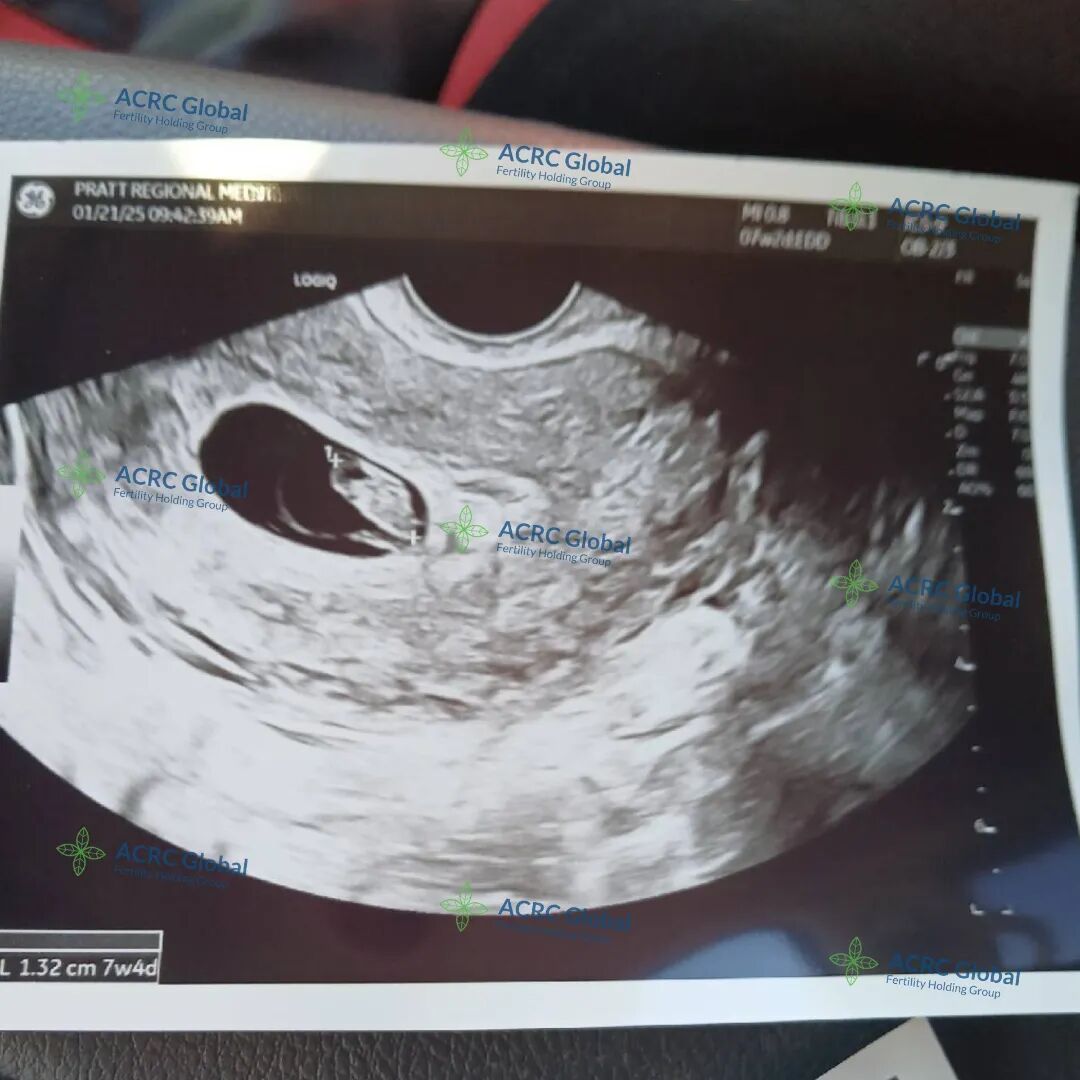

爱妈V的双胎移植也迎来了B超检查,两个宝宝都顺利着床了,宝宝A看起来非常活泼,一直在动,宝宝B则显得格外冷静,两个宝贝性格差异已经初见端倪,实在太有趣了!两位准爸爸听到这个好消息激动不已,已经约定好下一次产检时一同到场,为爱妈加油打气,给予满满支持!